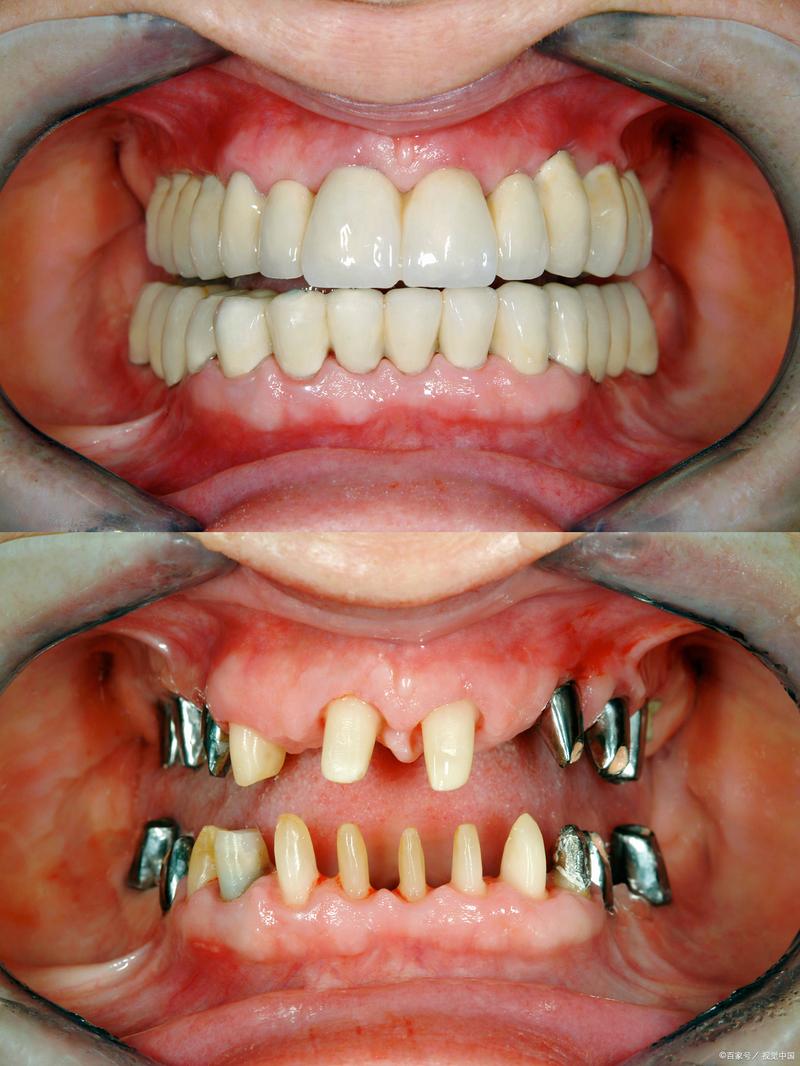

骨密度低是临床常见的骨骼健康问题,主要指单位体积骨组织内钙盐含量减少,骨结构稀疏,骨强度下降,常见于老年人、绝经后女性及长期服用某些药物(如糖皮质激素)的人群,牙齿缺失后,牙槽骨会因失去功能性刺激而逐渐吸收,导致骨量进一步减少,而骨密度低的状态会直接影响种植牙的成功率与长期稳定性,种植牙作为目前公认的牙齿缺失修复最佳方式,其核心原理是通过外科手术将种植体植入牙槽骨,依靠种植体与骨组织之间的“骨结合”实现功能恢复,骨密度低意味着骨质量下降,骨小梁稀疏、皮质骨变薄,种植体植入后初期稳定性难以保证,骨结合进程可能延迟,甚至增加远期种植体松动、脱落的风险,骨密度低患者种牙需更全面的评估与精细化的方案设计,以确保治疗效果。

骨密度低并非种植牙的绝对禁忌症,通过术前精准评估、个体化骨增量方案选择、优化种植体设计与术后长期维护,骨密度低患者仍可获得满意的种植效果,关键在于“多学科协作”(口腔种植科、骨科、内分泌科等)与“全程化管理”,从骨质量改善到种植体稳定,再到远期并发症预防,每个环节都需精细把控,最终实现功能与美观的双重恢复。